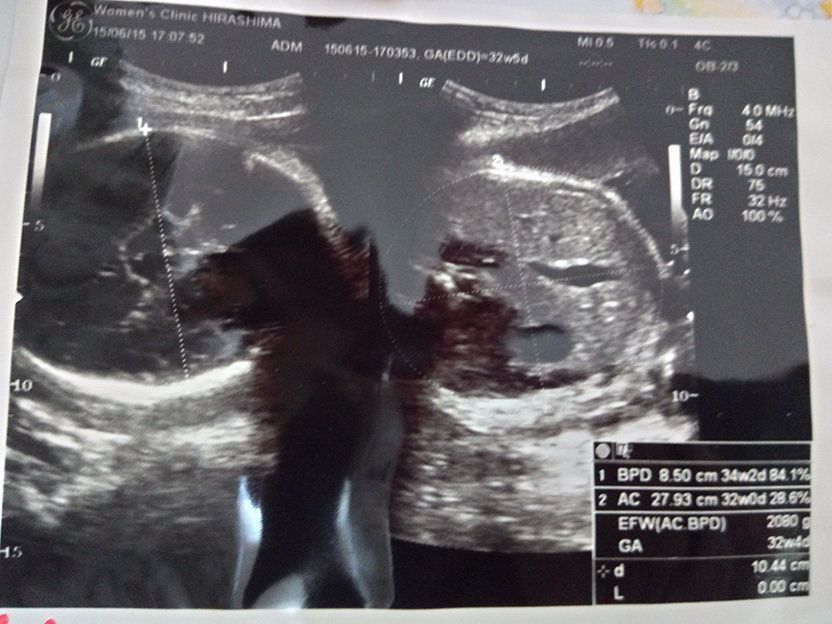

妊娠32週のエコー写真 赤ちゃんの推定体重2080g

この頃になると股関節痛が酷くなりました。少し歩いただけで、普通には歩けない状態になってしまい、道端でストレッチをしてしのいでいました。